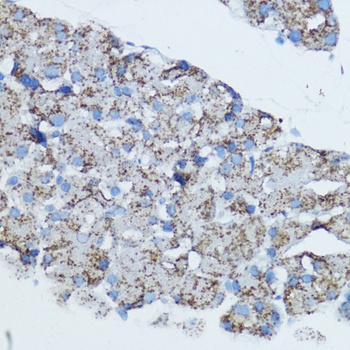

IF, IHC, WB

应用注释:WB: 1:1000 - 1:2000IHC: 1:50 - 1:200IF: 1:50 - 1:200